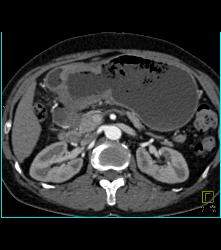

Antral Carcinoma With Celiac and Peri-portal Nodes